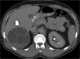

Complicated hydatid cyst